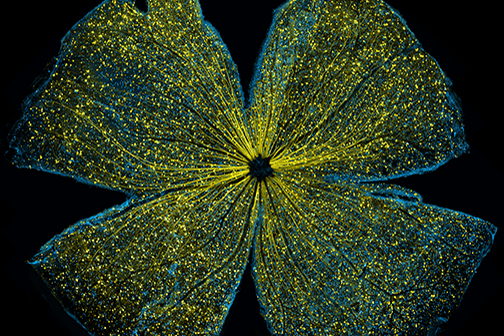

LSU Health New Orleans Develops New Human Cell Line to Study Blinding Eye Disorders

Under the direction of Boyd Professor Nicolas Bazan, MD, PhD, scientists at LSU Health New Orleans Neuroscience Center of Excellence have developed a new, experimental human cell line from retinal pigment epithelial cells. Called ABC, these cells so closely resemble and retain the properties of native retinal pigment epithelial (RPE) cells, the research team has shown that they are a reliable cell system to study retinal degenerative diseases. More

LSU Health Contributes to Research Suggesting Late-Onset Retinal Degeneration Mechanism & Potential Rx

A study led by the National Eye Institute (NEI) that included five researchers from the Bazan Lab at the LSU Health New Orleans Neuroscience Center of Excellence has discovered how late-onset retinal degeneration can develop and a surprising potential therapeutic -- metformin. The results are published online in Communications Biology, a Nature journal. More